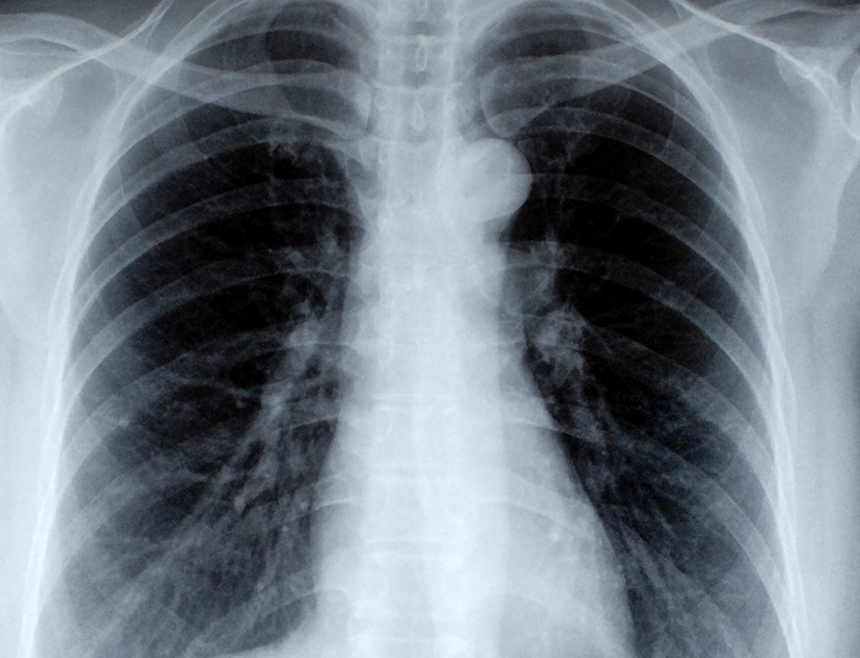

감염부위 : 폐의 폐포(하기도 감염)

증상 : 심한 기침, 가래, 가슴통증, 호흡곤란

따라서 폐렴은 '폐의 폐포(공기 주머니)에 염증이 생기는 호흡기 감염 질환'으로 감기보다 증상이 훨씬 심하며, 호흡곤란과 고열이 동반되므로 방치하면 생명이 위험할 수도 있는 질병이다.